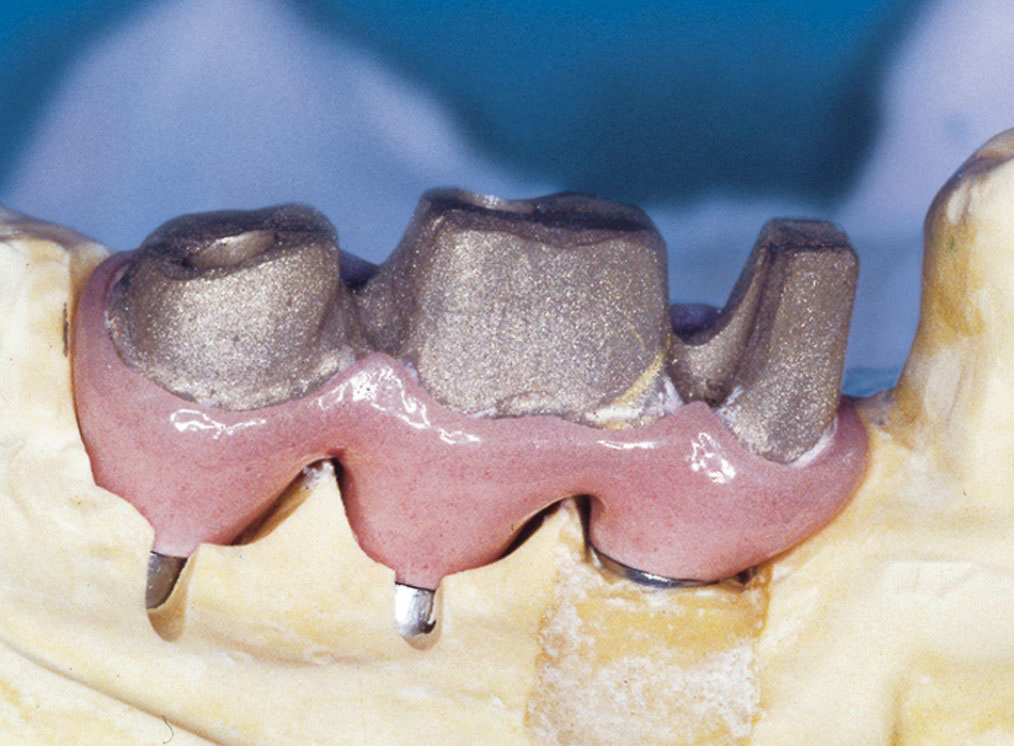

Protetické řešení může být pomocí můstku, který je kotvený na implantátech nebo pomocí jednotlivých korunek na implantátech.

V zásadě je možné do těchto můstků zařadit i přirozené zuby, zejména pokud je potřeba tyto zuby ošetřit proteticky – korunkami. Korunky nebo můstky mohou být na implantáty nacementovány nebo přišroubovány.

Pevné můstky – lepené nebo šroubované

S pomocí zubních implantátů můžeme díky různým kotevním systémům (třmeny, kulové hlavy, Locatory) zajistit stabilitu a držení protézy nebo při použití většího počtu implantátů zhotovit pevné náhrady – můstky nalepené nebo našroubované na pevno na implantáty.